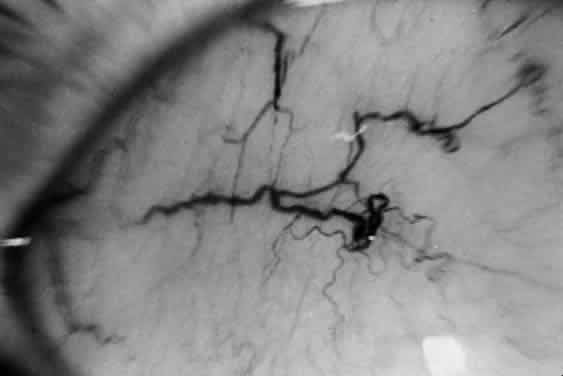

The principal ophthalmologic manifestation of MPS II is progressive retinal degeneration with attendant impairment of vision.21,51 Night vision problems and visual field defects are common. The disorder may lead to blindness. The fundus signs include retinal pigmentary changes, sometimes spicule formation, retinal arteriolar attenuation, and optic disc pallor. The ERG is usually reduced or extinguished21,22,52; in some cases it is normal.22 In addition, bilateral epiretinal membranes with tortuosity of the retinal vessels has been reported as an unusual finding in two brothers with Hunter syndrome type B.53

Swelling of the nerve head is a frequent finding in Hunter syndrome; it may be due to increased intracranial pressure or mucopolysaccharide deposition in and around the optic nerve.44,54–56